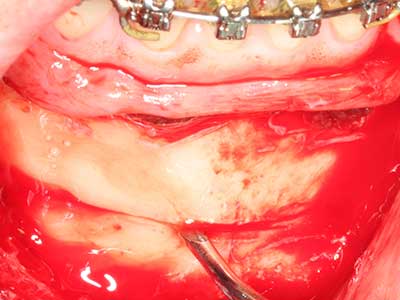

Fig. 18: Preparation of a cortical cover with the piezo bone saw (Piezomed, W&H).

Fig. 19: Surgical site after neurolysis and removal of osteoma.

Fig. 20: The removed bone cover is re-adapted and fixed with an osteosynthesis screw (KLS Martin, Tuttlingen).